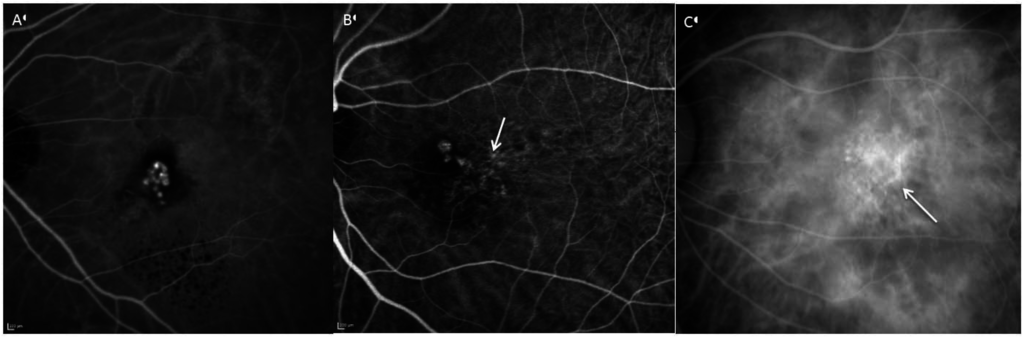

6. Angiography

- Cheung, C.M.; Lai, T.Y.; Chen, S.J.; Chong, V.; Lee, W.K.; Htoon, H.; Ng, W.Y.; Ogura, Y.; Wong, T.Y. Understanding indocyanine green angiography in polypoidal choroidal vasculopathy: The group experience with digital fundus photography and confocal scanning laser ophthalmoscopy. Retina 2014, 34, 2397–2406. [Google Scholar] [CrossRef] [PubMed]